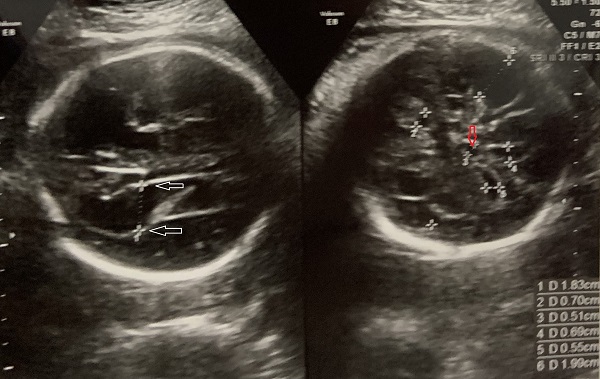

Cuerpo calloso: es una estructura compuesta por haces nerviosos cuya función es la de conectar e integrar regiones corticales homólogas entre ambos hemisferios cerebrales. Su ausencia total puede conducir a problemas cognitivos y del desorrollo psicomotriz o pasar totalmente desapercibida. Su ausencia parcial, paradójicamente, se asocia con peor pronóstico. Como estructura ecográfica, es una de las más bellas que hay en el cerebro pero, para obtenerla se requiere pericia y muy buena resolución ecográfica. Sus alteraciones congénitas son diagnóstico de problemas primarios del desarrollo cerebral y se manifiestan con cambios indirectos en otras secciones cerebrales, especialmente ventriculomegalia.

Lesiones cerebrales

En este resúmen gráfico se incluye la mayor parte de las lesiones cerebrales congénitas visibles en vida fetal; los cortes transversales expuestos aquí son insuficientes para algunas de ellas y los hallazgos pueden modificarse en el tiempo, usualmente manifestando mayor número de elementos anómalos. Muy pocas condiciones mejoran con el tiempo

Tomado de HN Xie et al. Using deep learning algorithms to classify fetal brain ultrasound images as normal or abnormal. Ultrasound Obstet Gynecol